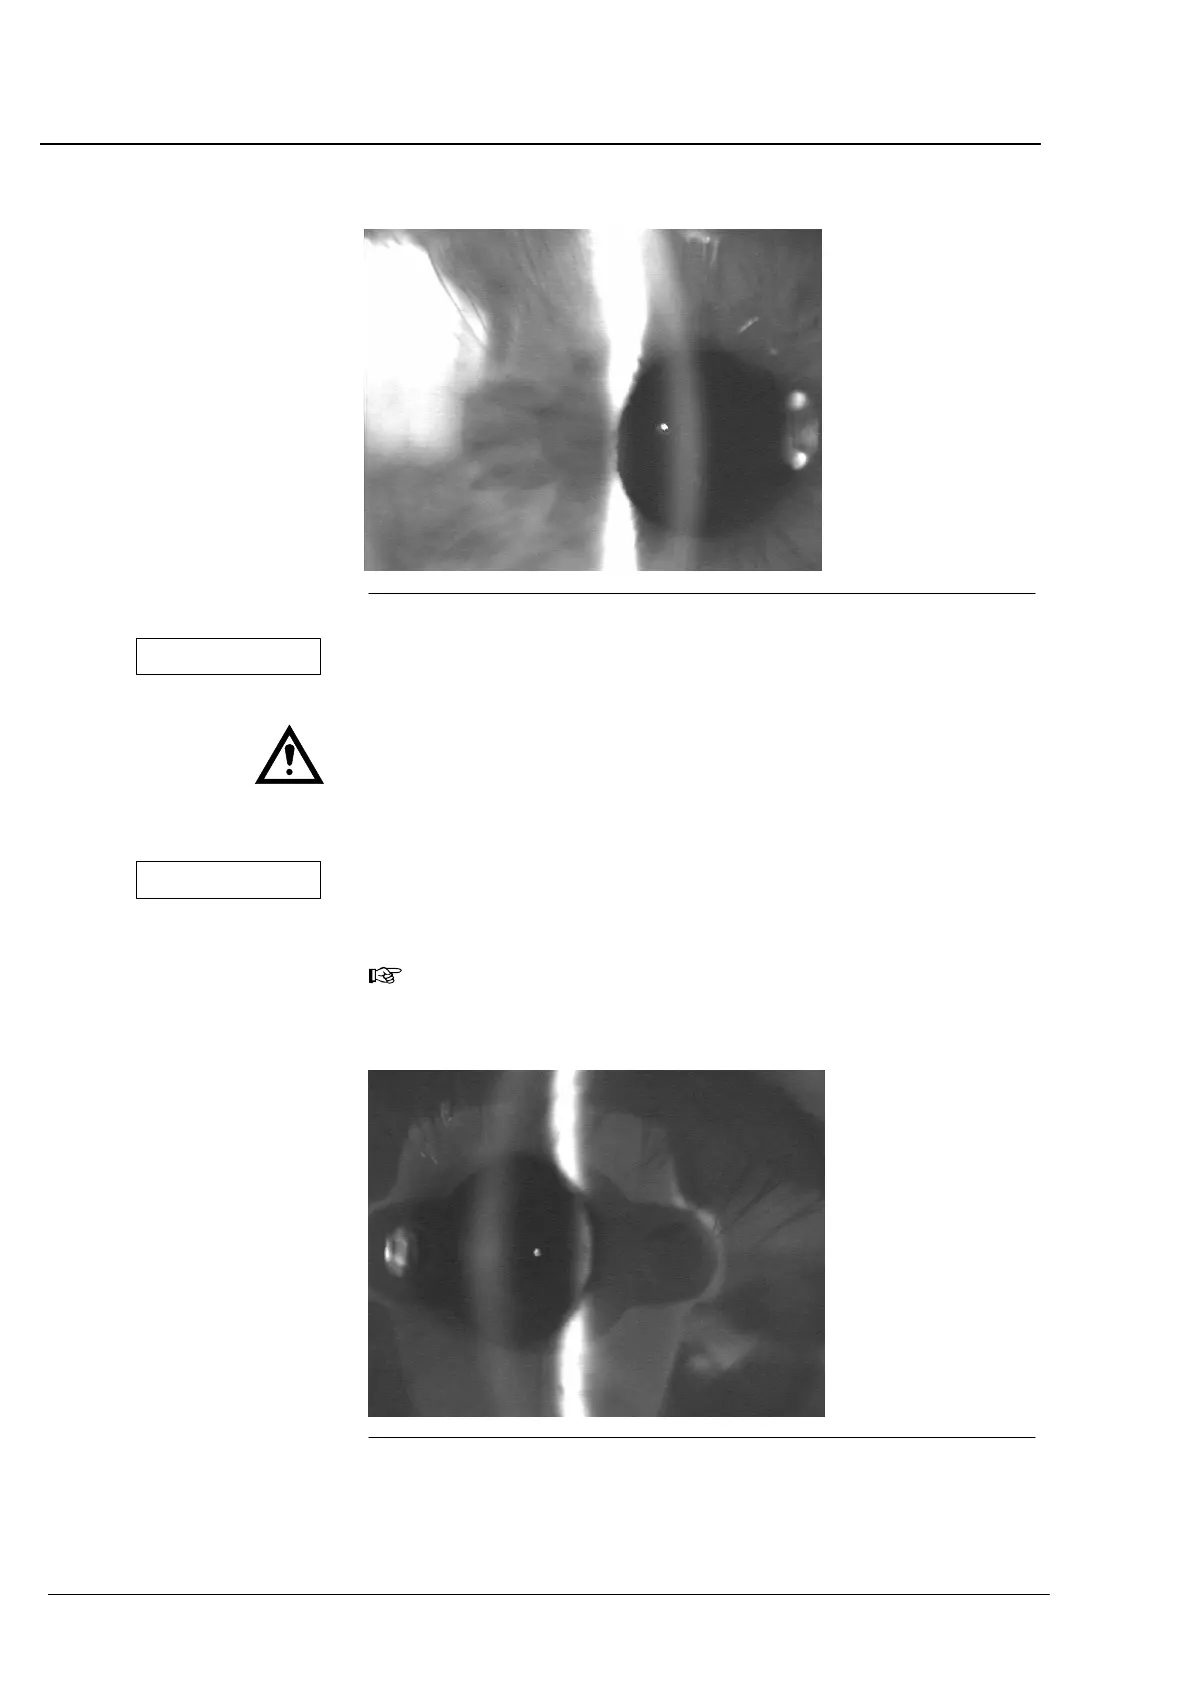

Fig. 67 Image de fente sur l'iris (la lentille n'est pas visible)

Dans un tel cas, l'image de fente sur l'iris est (presque) reconnaissable

de manière continue. Le programme d'évaluation automatique ne

reconnaît pas comme tel ce faux réglage. Les valeurs mesurées sont trop

petites. Ces valeurs ne correspondent pas à la profondeur de la

chambre antérieure, elles indiquent la distance entre la face avant de la

cornée et l'iris. En aucun cas, la valeur affichée représente la valeur

mesurée exacte de la profondeur de la chambre antérieure!

Fig. 68 Arête avant de la lentille faiblement visible

L'image suffit pour l'évaluation de la profondeur de la chambre

antérieure (sur cette image, on peut reconnaître comme artefact non

perturbateur le côté avant de l'IOLMaster).